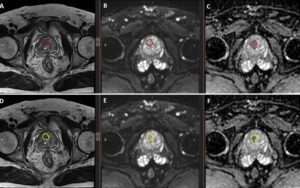

After pre-processing, the next critical step is segmentation. This involves accurately delineating the boundary of the prostate lesion on the MRI scans, typically on a slice-by-slice basis to create a 3D volume of interest (VOI). Segmentation can be done manually by a radiologist, semi-automatically with software assistance, or fully automatically using advanced AI algorithms. The quality of the segmentation is paramount, as an inaccurate boundary will lead to the extraction of flawed and unreliable radiomic features.

One of the primary applications of radiomics is in lesion classification—differentiating benign prostate conditions, like hyperplasia or prostatitis, from malignant cancer. Machine learning models trained on radiomic features have shown great promise in accurately identifying cancerous lesions. These models can learn the subtle patterns of shape, intensity, and texture that distinguish different tissue types.

Furthermore, radiomics can help in risk stratification. For patients diagnosed with prostate cancer, radiomic features have been shown to correlate with the Gleason score, a key indicator of tumor aggressiveness. A model might learn, for example, that a highly irregular shape combined with a heterogeneous texture is strongly associated with a high Gleason score. This information can help clinicians determine the most appropriate course of action, whether it be active surveillance for low-risk disease or immediate intervention for more aggressive cancer.